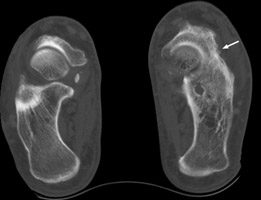

Calcaneonavicular coalition

Plain film and CT images of calcaneonavicular coalition. Notice the elongated, tubular like extension of the anterior calcaneus seen on the lateral film; this imagery has been likened to the elongated nose of an anteater. There is abnormal bony fusion of the calcaneus and navicular bones, with the presence of a bony bar extending between these two bones.